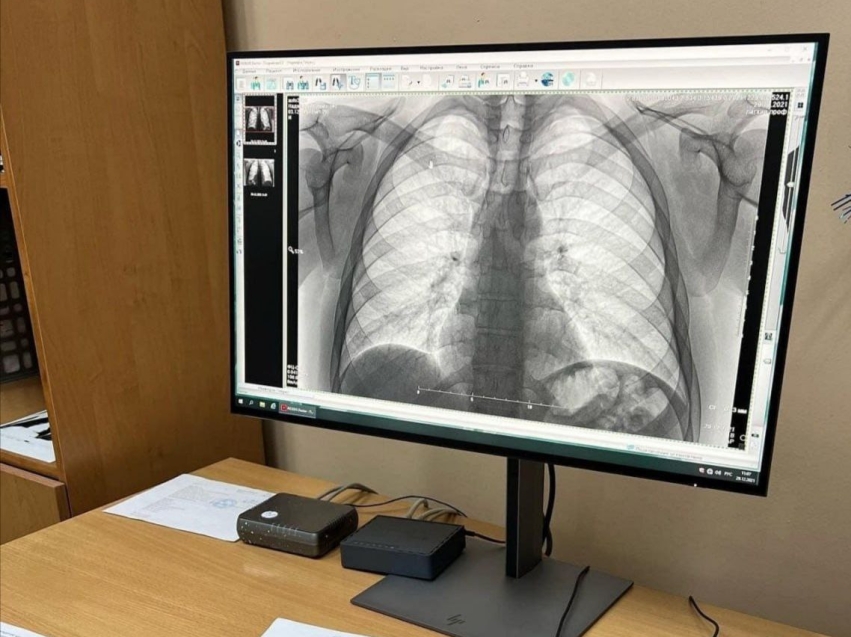

Краевой фтизиопульмонологический центр и благотворительная общественная организация «Пища жизни» проводят профилактическую акцию для жителей отдаленных районов Читы. Пациенты сразу получат результаты, при необходимости врач направит на дополнительные обследования.

Жители отдалённых районов Читы смогут пройти бесплатное флюорографическое обследование

Фото пресс-службы министерства здравоохранения Забайкальского края